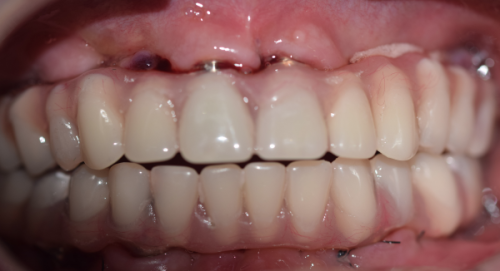

骨结合完成后,就进入了安装基台和牙冠的阶段。这一步相对较快,一般在几周内就可以完成。医生会先安装连接种植体和牙冠的基台,然后取牙齿模型,制作适合患者口腔的牙冠,末尾将牙冠安装在基台上,整个种植牙的修复过程就完成了。

手术前,患者需要进行口腔全方面检查。这包括口腔X光片、CT等检查,医生可以通过这些检查了解患者的牙槽骨情况、牙齿状况以及口腔内是否存在炎症等问题。只有在确定患者的口腔条件适合种植牙手术的情况下,才能进行手术。如果检查发现有问题,可能需要精良行相应的治疗,这就会增加整个治疗的时间。